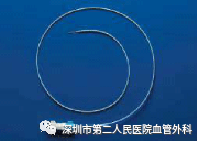

CDT是将带有很多侧孔的溶栓导管,通过静脉穿刺的方法插入血栓中,将溶栓药物通过侧孔持续推注到血栓中,可获得很好的溶栓效果(图10-12)。这种方法对静脉壁损伤轻微,而且能较好地保护静脉瓣的功能。

图10 带有侧孔的溶栓导管